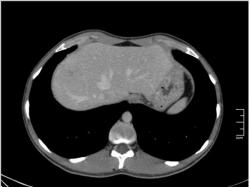

КТ печени. Наблюдения для размышления.

Уважаемые коллеги, особенно врачи КТ. Надеюсь что данная публикация окажется полезной для многих из Вас. Ниже представлены сканы печени; предлагаю Вам ознакомится с ними и высказать свое мнение. Пациент мужчина средних лет, специфичных жалоб не предъявляет.

Если Вы не против, я немного придержу продолжение данного наблюдения. Основная задача данной публикации не сам диагноз, а показать современные аспекты и особенности метода КТ, а также важность глубины и объёма знаний врачей радиологов которые занимаются КТ диагностикой.

Уважаемый v1tal! Огромная Вам благодарность; Вы назвали ключевое слово: фаза! Высказанная Вами мысль, это моя основная цель данной публикации. Постараюсь позже более детально объяснить почему. Представленные сканы выше, были выполнены на стандартной портальное фазе. А сейчас, я покажу сканы данного пациента выполненные на артериальной фазе :

Да Ola la, Вы абсолютно правы; это Фокальная Нодулярная Гиперплазия печени (FNH Focal Nodular Hyperplasia). Одна из немногих гиперваскулярных опухолей печени. Наверное некоторые коллеги спросят, и зачем было изначально публиковать портальную фазу, на которой «не видно» (хотя опухоль видна, пусть и не напрямую, и Nela это доказала); и только потом показывать сканы на артериальной фазе, на которой всё «красиво и показательно». Постараюсь объяснить.

За эти два года, в течении которых я познакомился с радиологическим русскоговорящим интернетом, я пришёл к определённым выводам. К сожалению, при наличии уже довольно неплохого парка современной аппаратуры в клиниках России и СНГ (у меня лично аппаратура намного скромнее по возможностям чем например у Nela или v1tal), ощущается огромный пробел в знаниях очень многих врачей, которые работают на этих аппаратах. И как следствие, врачи классические рентгенологи, отправляя пациентов на до-обследование в эти клиники, получая при этом неудовлетворительный результат проведённых исследований, начинают полагать (и имеют на это право), что зачем все эти «КТ и МРТ», если мы по своим стандартным рентгенологическим методикам получаем тот же результат (если иногда и не лучше-живой пример тому публикация vital с дивертикулом пищевода, где врач КТ написал диафрагмальную грыжу). И когда я читаю такие посты, мне становится очень обидно, хотя повторюсь, я уже пониманию причины такого мышления. Тем более что мало кто знает, что КТ и МРТ это не «статические методики», при которых взял пациента, положил на стол, дал контраст (как, куда, на какой скорости-мало кого волнует), сделал одну спираль/фазу, и до свиданья, «подавайте» следующего. Современные протоколы КТ и МРТ выработаны ПОД КАЖДЫЙ КОНКРЕТНЫЙ ДИАГНОЗ, иными словами, если мы подозреваем заболевание кишечника, и снимем пациента по протоколу разработанному для диагностики патологии печени или поджелудочной, то мы можем пропустить «всё на свете» в кишечнике, и при этом ничего не найти в печени или панкреас.